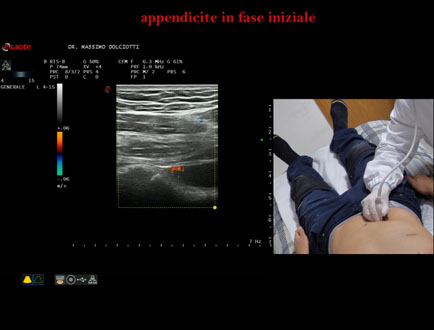

Data inserimento: 13/11/2025

Ecografia del: 10/11/2025

Strumento: Esaote MyLab Eight

Sonda: Lineare Multifrequenza 4-15 MHz

Età Paziente: M 26 anni

Motivazione dell'esame: da 2 settimane dolori addominali.

Commento all'esame: le immagini ed il video documentano il verme appendicolare, dello spessore trasversale di 9,1 mm e diametro longitudinale di 8,8 mm, con scarsi segnali di vascolarizzazione, da ricondurre ad appendicite in fase iniziale.

Conclusioni: appendicite in fase iniziale (early appendicitis).

Presentazione: Dr. Massimo Dolciotti - Ancona

Elaborazione digitale: Andrea Dini - Ancona